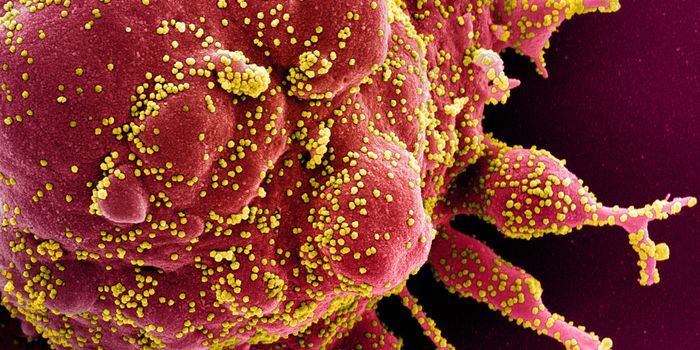

APR 04, 2022Cell & Molecular BiologyAbout 1.5 million new HIV infections are thought to have occurred last year, and while COVID-19 has dominated concerns a ...

FEB 21, 2022Cell & Molecular BiologyTwo people have been cured of HIV, and now, a US woman joins them. In this third case, stem cell transplants were being ...

NOV 30, 2021ImmunologyHIV is a master of disguise. Once the virus enters the body, it has a number of sophisticated mechanisms through which i ...

NOV 22, 2021MicrobiologyThough treatments are available, there is no cure or vaccine from HIV, which impacts about 38 million people worldwide. ...

SEP 06, 2021MicrobiologyHIV vaccines have remained elusive in part because the virus has a powerful ability to mutate, and there are so many str ...

JUN 24, 2021ImmunologyA new study has revealed how stem cells can be used to amplify immune responses to HIV, the virus that causes AIDS. The ...